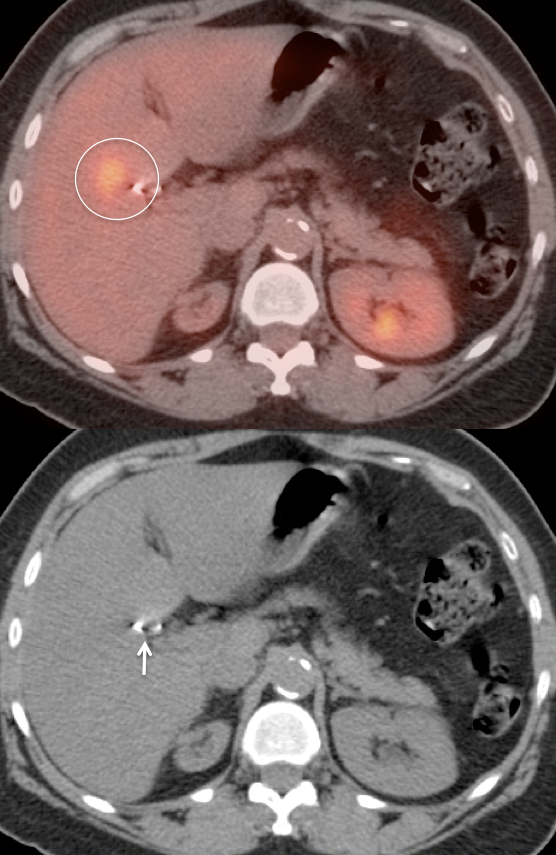

PET/CT Interpretation of Gallbladder Activity:

The normal gallbladder typically demonstrates little or no FDG uptake.

Mild to moderate diffuse gallbladder uptake is usually normal.

Intense diffuse gallbladder uptake in an otherwise normal appearing gallbladder often represents normal physiologic uptake. Ultrasound correlation, however, is still typically recommended: “Ultrasound correlation may be of diagnostic value, if clinically warranted.”

Diffuse intense gallbladder uptake associated with wall thickening, pericholecystic fluid or gallstones is suspicious for cholecystitis. In such cases, ultrasound correlation is strongly recommended, “Ultrasound correlation is recommended in this case to exclude acute cholecystitis.”

While focal intense gallbladder wall uptake can be seen with benign polyps, adenomyomatosis or focal inflammation associated with cholecystitis, malignancy must be excluded.